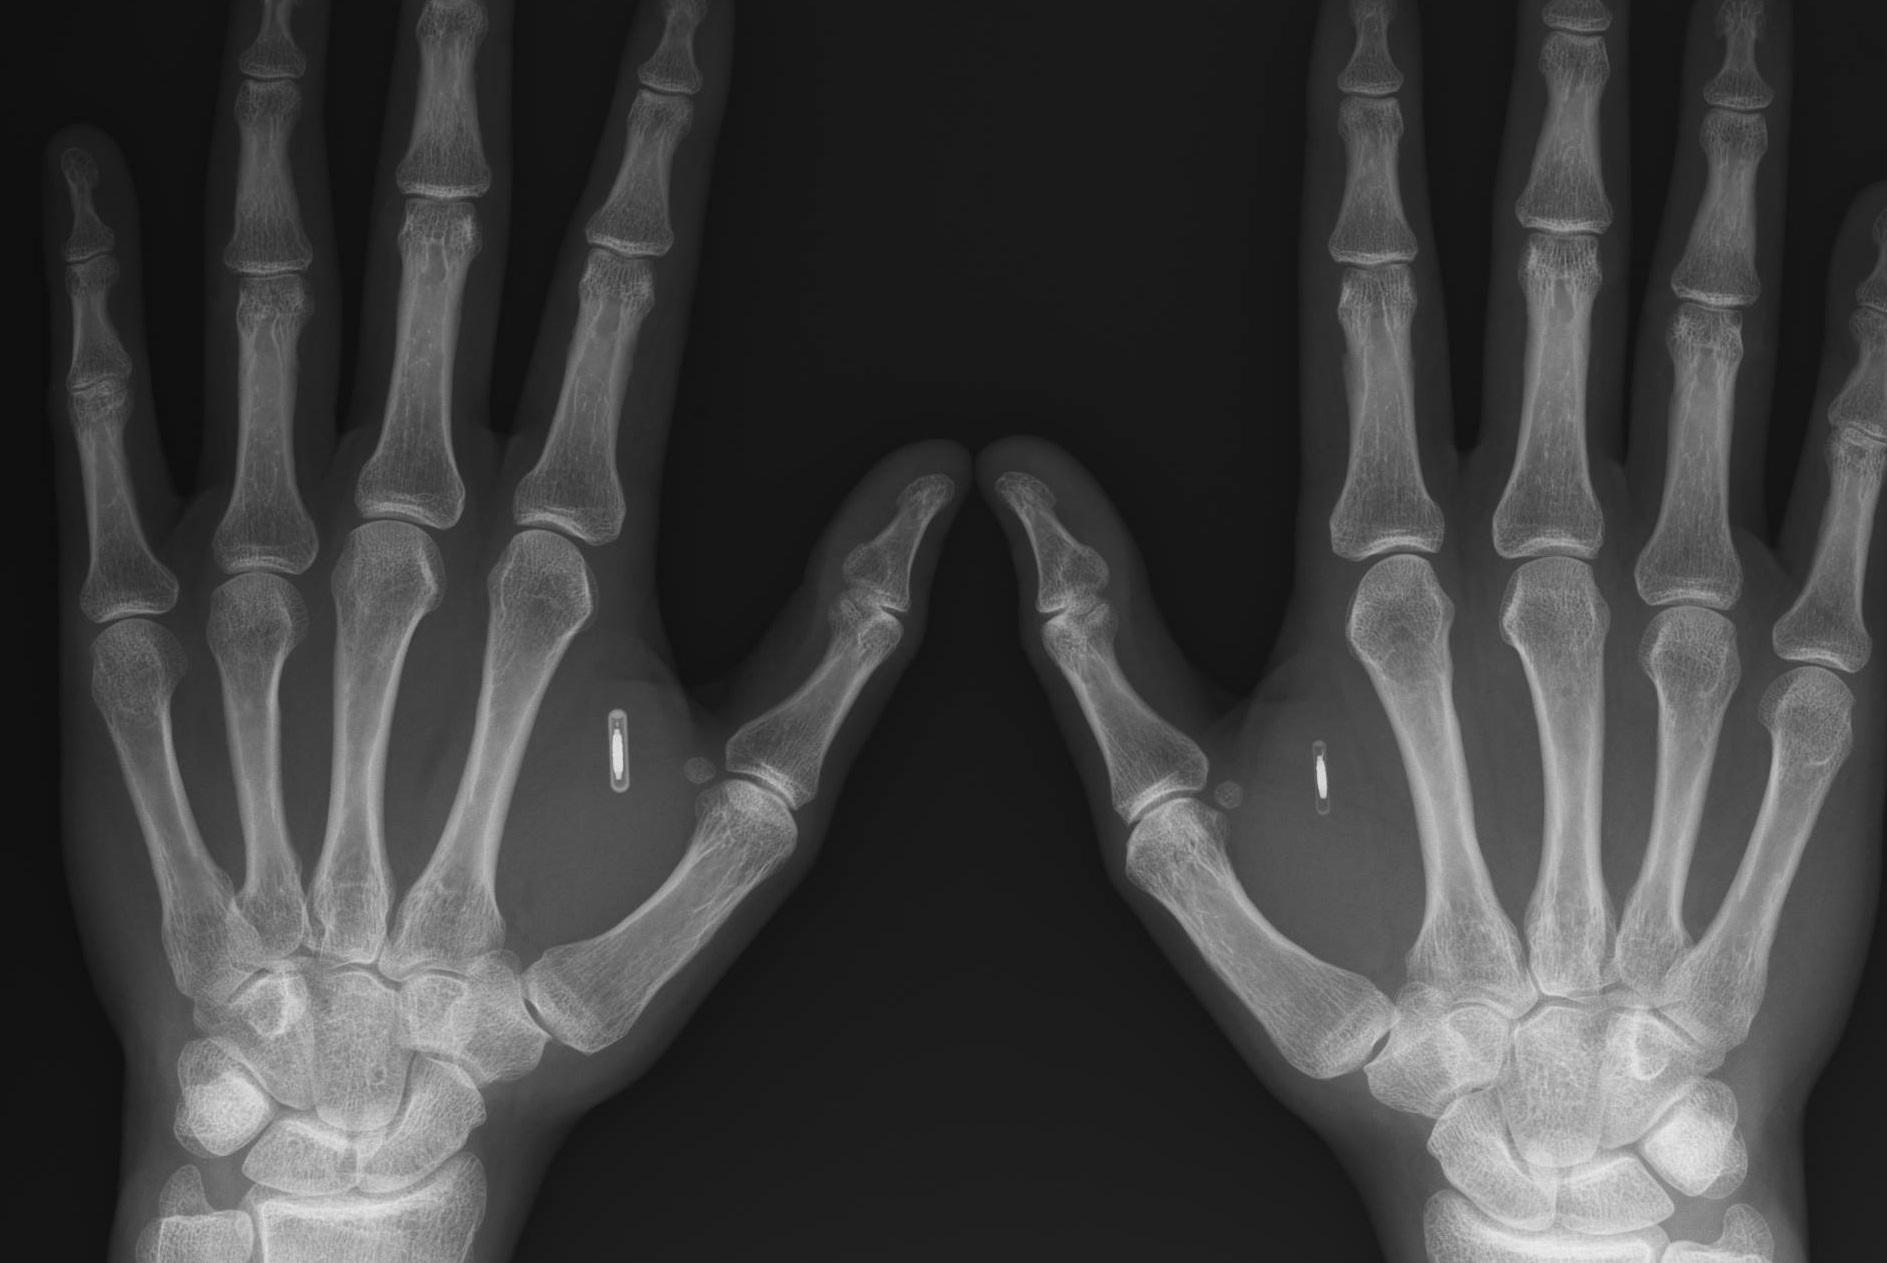

Nearly two thirds of people in leading Western European countries would consider augmenting the human body with technology to improve their lives, mostly to improve health, according to research commissioned by Kaspersky, a multinational cybersecurity company.

The Opinium Research survey of 14,500 people in 16 countries including Britain, Germany, France, Italy and Spain showed that 63 per cent of people would consider augmenting their bodies to improve them, though the results varied across Europe.

The survey found that most people wanted any human augmentation to work for the good of humanity, though there were concerns that it would be dangerous for society and open to exploitation by hackers.